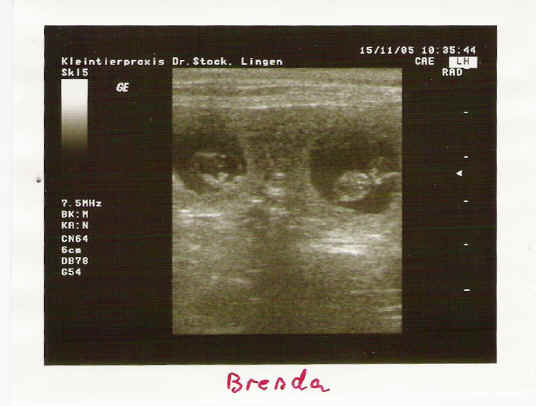

Neue US - Aufnahmen vom 31. Tag der Tragzeit von Brenda v. Weinbacher Land.

Eine Hündin trägt ca.63 Tage, mal mehr, mal weniger. Unsere Hündin hat sich den 64. Tag ausgesucht. Nach 5 -6 Wochen kann man der Hündin sehr gut ansehen, dass Sie tragend ist, denn der Bauchumfang hat stark zugenommen und das Gesäuge ist stark abgeschwollen. Hier sieht man eine Hündin mit einer Tragzeit von 50 Tagen. Vom rechten Horn ist nur der zum Geburtsweg führende Teil dargestellt.